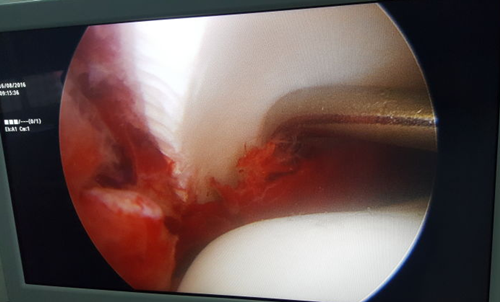

图为术中操作

境下用探钩清理骨折断端软组织及血凝块